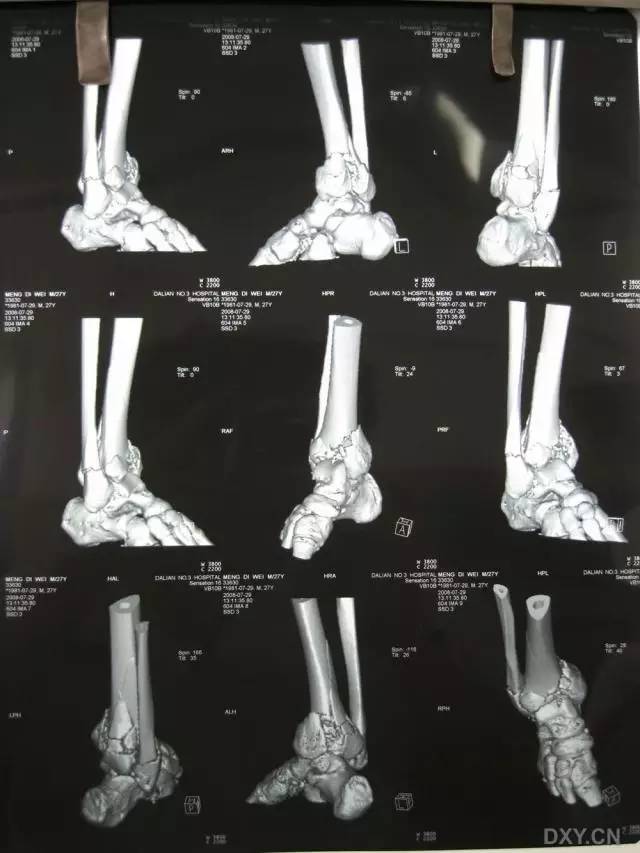

6. Pilon 骨折

涉及负重关节面(胫距关节面)与胫骨远侧干骺端的骨折。其典型特征是干骺端存在不同程度的压缩、干骺端的压缩粉碎性骨折不稳定、原发性关节软骨损伤以及永久性关节面不平整导致预后不良。

pilon 骨折正位片

pilon 骨折侧位片

pilon 骨折三维 CT 表现